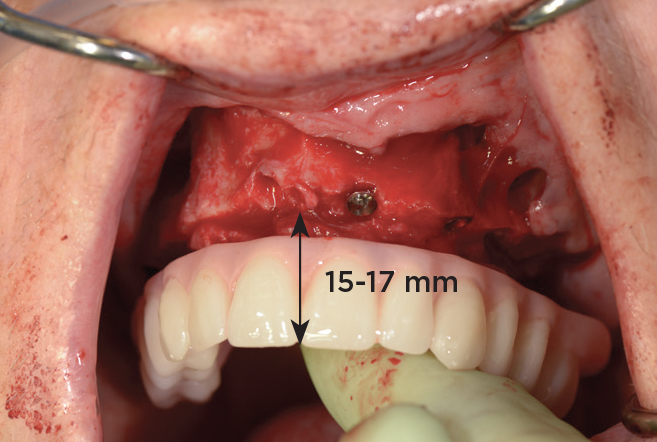

An important advantage of this approach is the ability to simulate bone reduction on the models and verify the presence of 15 mm to 17 mm and 13 mm to 15 mm of required inter-occlusal space for maxillary and mandibular restorations, respectively. This creates a platform for a diagnostic wax-up of the proposed dental rehabilitation and fabrication of wax prosthesis try-ins when necessary. Finally, a modified All-on-4 provisional prosthesis surgical and restorative guide developed by the authors for restoration-driven surgery and simplified restorative procedures is fabricated (Figure 2 through Figure 8).

Fig 4. Diagnostic wax-up performed after model surgery simulating maxillary tooth extraction. Note that inferior repositioning of the incisal plane helped create the 15 mm to 17 mm inter-occlusal space needed for the maxillary All-on-4 provisional restoration.

Figure 4

Fig 5. Bone reduction model surgery performed in mandibular arch to create 13 mm to 15 mm of inter-occlusal space required for the mandibular All-on-4 provisional restoration.

Figure 5